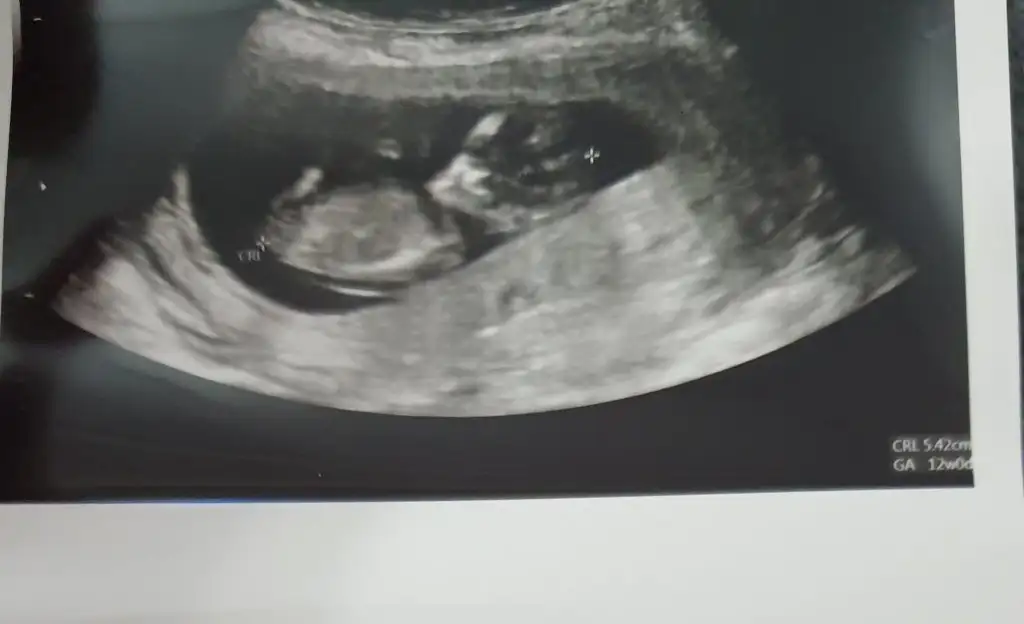

Erkek gibi sanki eminde olamadim çok parlak USG 11 12 13 haftalar olmalı

11 12 13 haftalar olmalı sanki erkek ama şimdilik bu haftalarda iki tarafa benzer tekrar USG bekliyorumIkra meyra Hanım buraya sizin için üye oldum

Teşekkür ediyorum doktor da büyük ihtimal erkek gibi dediErkek gibi sanki eminde olamadim çok parlak USG 11 12 13 haftalar olmalı